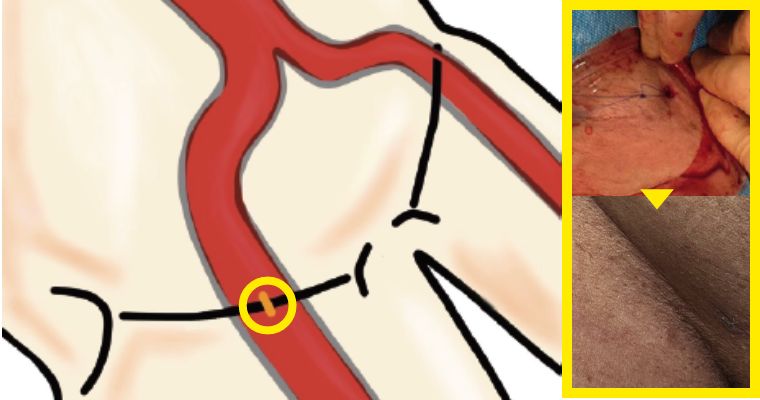

併存疾患や年齢により人工血管置換術に耐えれない方に向けて、体への負担が少ない治療が開発されました。

足の付け根の血管から、カテーテルを使用して人工血管(ステントグラフト)を大動脈に挿入し、大動脈瘤破裂を防ぐ治療になります。

当院では皮膚を切開しないで行うステントグラフト治療を積極的に施行しております。他施設に先駆けて2013年から皮膚を切開しないでステントグラフト治療を行い、胸部大動脈瘤でも導入しております。導入から500例を超える症例に皮膚を切開しないステントグラフト治療を行いましたが、入院日数は平均3-6日です。局所麻酔で行うため、全身麻酔が困難といわれた方に対しても安全に治療をしています。

腹部大動脈瘤破裂に対して施行した緊急ステントグラフト内挿術